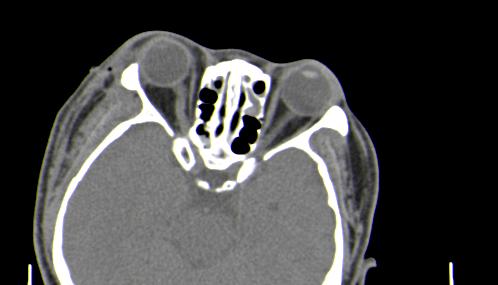

以下是引用皎皎白驹在2006-11-29 8:48:00的发言:[br]影像表现:双侧筛窦和上颌窦、鼻腔内均密度增高,右侧视神经增粗、弯曲,左筛窦顶部筛板及右侧纸板近视神经孔区可见骨折线。[br]结合临床表现考虑:右侧筛窦纸板近视神经孔区骨折致右侧视神经损伤。最好做个眼眶冠状扫描,更明确右侧视神经管是否狭窄。

以下是引用w_jianhua在2006-11-29 10:07:00的发言:[br]影像表现:双侧筛窦和上颌窦、鼻腔内均密度增高,右侧视神经增粗、弯曲,左筛窦顶部筛板及右侧纸板近视神经孔区可见骨折线。[br]结合临床表现考虑:右侧筛窦纸板近视神经孔区骨折致右侧视神经损伤。最好做个眼眶冠状扫描,更明确右侧视神经管是否狭窄。 [br] [br]支持[br]

以下是引用守望可可西里在2006-11-29 9:46:00的发言:[br][quote]以下是引用皎皎白驹在2006-11-29 8:48:00的发言:[br]影像表现:双侧筛窦和上颌窦、鼻腔内均密度增高,右侧视神经增粗、弯曲,左筛窦顶部筛板及右侧纸板近视神经孔区可见骨折线。[br]结合临床表现考虑:右侧筛窦纸板近视神经孔区骨折致右侧视神经损伤。最好做个眼眶冠状扫描,更明确右侧视神经管是否狭窄。